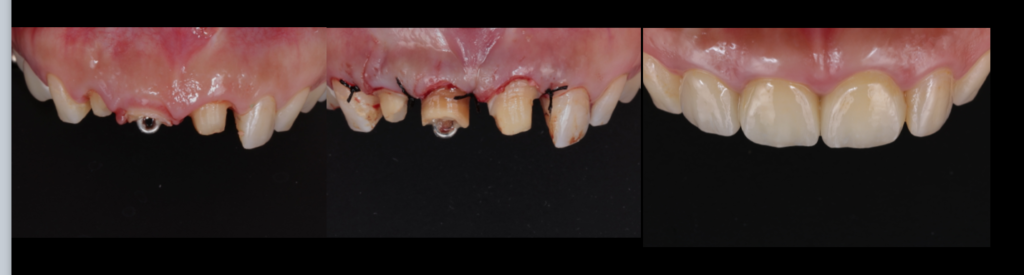

前歯の治療、本当にセラミックが最善ですか?

― 前歯だからこそ「ダイレクトボンディング」という選択 ―

前歯の見た目が気になり、「セラミックを入れたほうがいいですか?」とご相談を受けることがよくあります。

確かにセラミックは美しく、耐久性の高い治療法です。しかし、すべて…